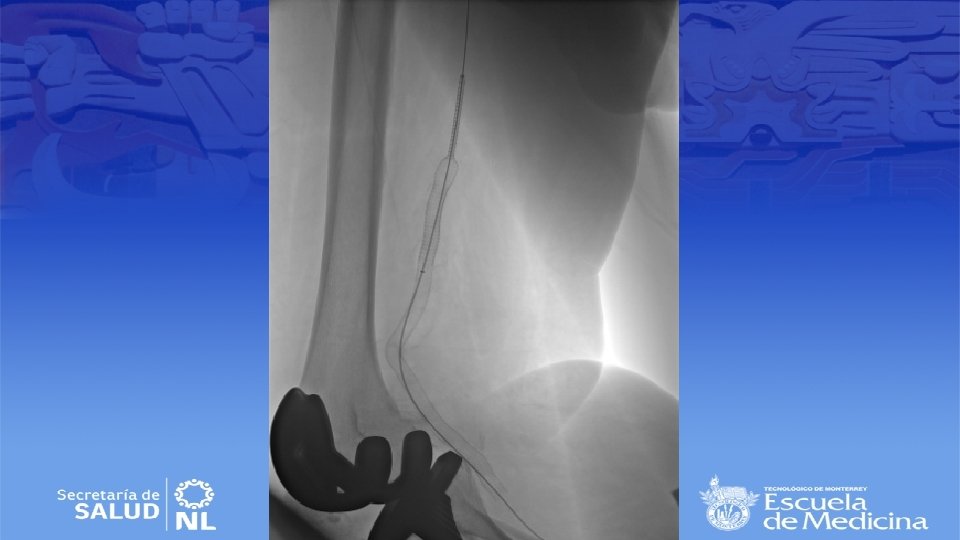

Cirugía endovascular • Para pacientes con alto riesgo quirúrgico • Deben de tener al menos 2 cm de arteria proximal y distal sin patología para anclar la endoprótesis • Se repite la angiografía durante el procedimiento para selección de la endoprótesis correcta • Debe de ser 10 a 15% mas grande que el diámetro del vaso

Resultados • Pacientes asintomáticos: permeabilidad a 5 años 85% y conservación de extremidad 95% • Pacientes sintomáticos: permeabilidad a 5 años 60% y conservación de extremidad 70% • Terapia endovascular a las 12 meses la permeabilidad se encuentra entre 75 – 100%. A 36 meses 80 – 85%.